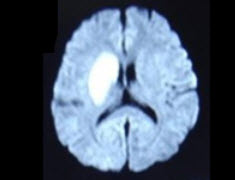

49岁,女性,有轻瘫,头痛,CT表现如图,最可能的诊断是( )

A:硬膜下血肿

B:硬膜下积液

C:Dandy-Walker综合征

D:脑积水

E:蛛网膜囊肿